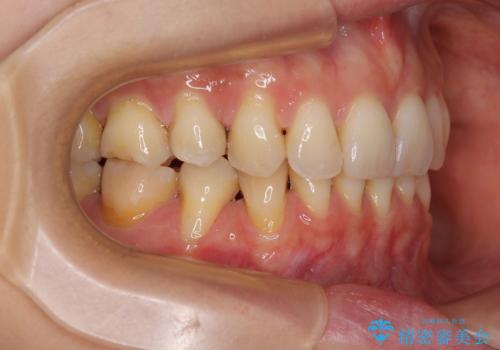

- 歯肉が薄く、退縮して露出した歯根を気にして来院された患者様です。

元々歯肉が非常に薄いことが推察され、抜歯矯正による移動が大きかったのか、歯肉が退縮している状態でした。